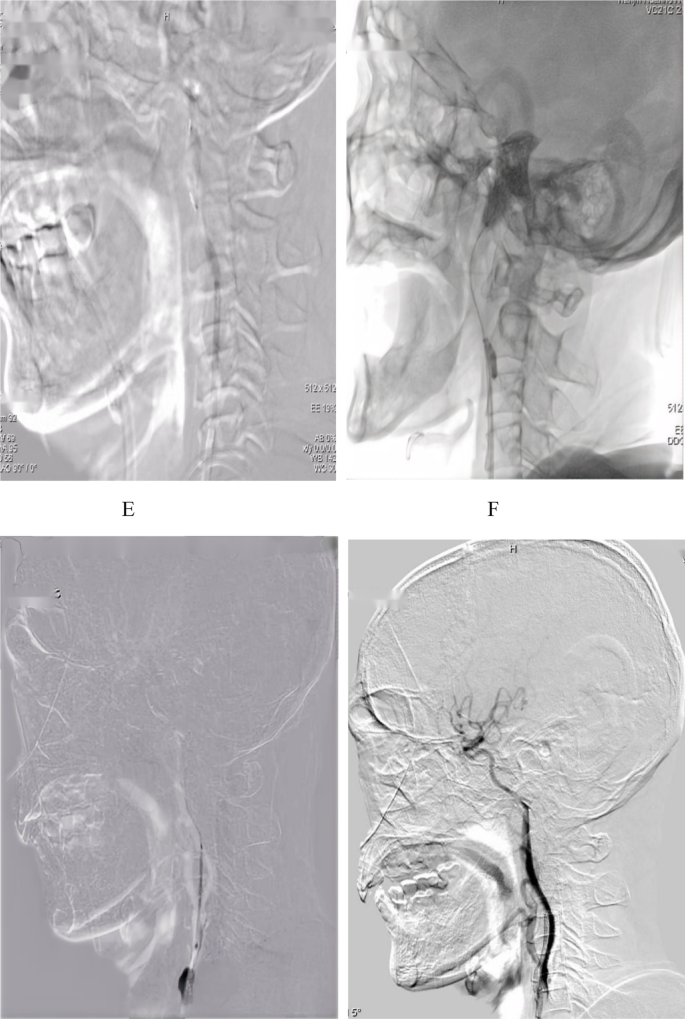

A 65-year-old male patient presented with the left carotid artery occlusion. (A,B) Angiography revealed occlusion of symptomatic cervical internal carotid artery (sICAO). (C) BGC was inflated to block proximal blood flow, and a microcatheter was advanced over a microwire across the occluded segment into the true lumen. (C) Using an exchange technique, a distal EPD was deployed in the petrous segment of the internal carotid artery. (D) Balloon angioplasty was used to open the blocked area, creating a endovascular pathway. (E) After establishing the endovascular pathway, the distal EPD was retrieved under negative pressure. (F) BGC was inflated to block proximal blood flow while the large-bore catheter continued to aspirate residual thrombus from the carotid artery. (G) BGC was utilized to occlude proximal blood flow during the deployment of the carotid artery stent. (H) Post-stenting angiography demonstrated complete vascular recanalization, indicating that the stent had been successfully released.